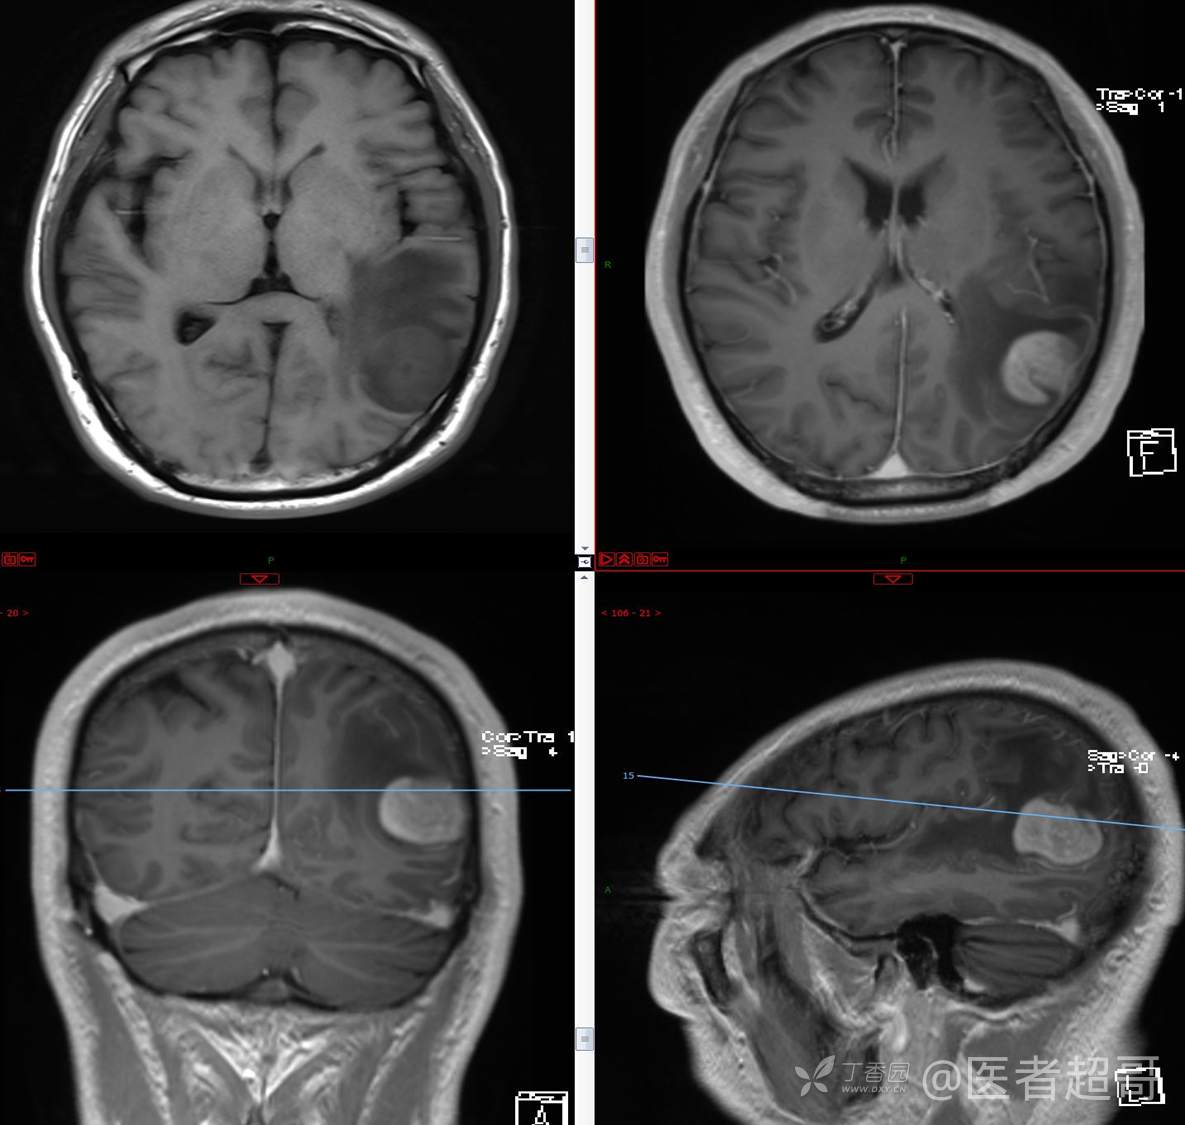

比较典型病例,CT、MRI齐全,请分析,领丁当!

男,56岁

主 诉:查体发现颅内占位10天。

现病史:患者于约10天前于我院查体时行颅脑MRI提示左侧顶叶占位病变,无头痛头晕,无恶心呕杜,无肢体活动不利,无感觉异常,现患者为求进一步治疗,就诊于我科门诊,门诊以“颅内占位性病变”收入我科。患者自发病以来,神志清,精神可,饮食及睡眠差,大小便无明显异常,体重无明显变化。